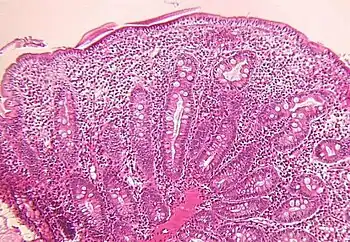

a,b)Moderate/severe shortening of most villi c)focal superficial epithelial d) crypt architectural changes.

Small intestine biopsy of a patient with THE syndrome showing severe villous atrophy with intense mononuclear cell infiltration in the lamina propria. (Courtesy of Prof. Michel Peuchmaur, Hôpital Robert Debré, Paris, France)

Microscopic examination of a biopsy of the small bowel in these patients shows villous atrophy with low or no mononuclear cell infiltration of the lamina propria nor specific abnormalities involving the epithelium. The amount of villous atrophy does not explain the severity of the diarrhea.